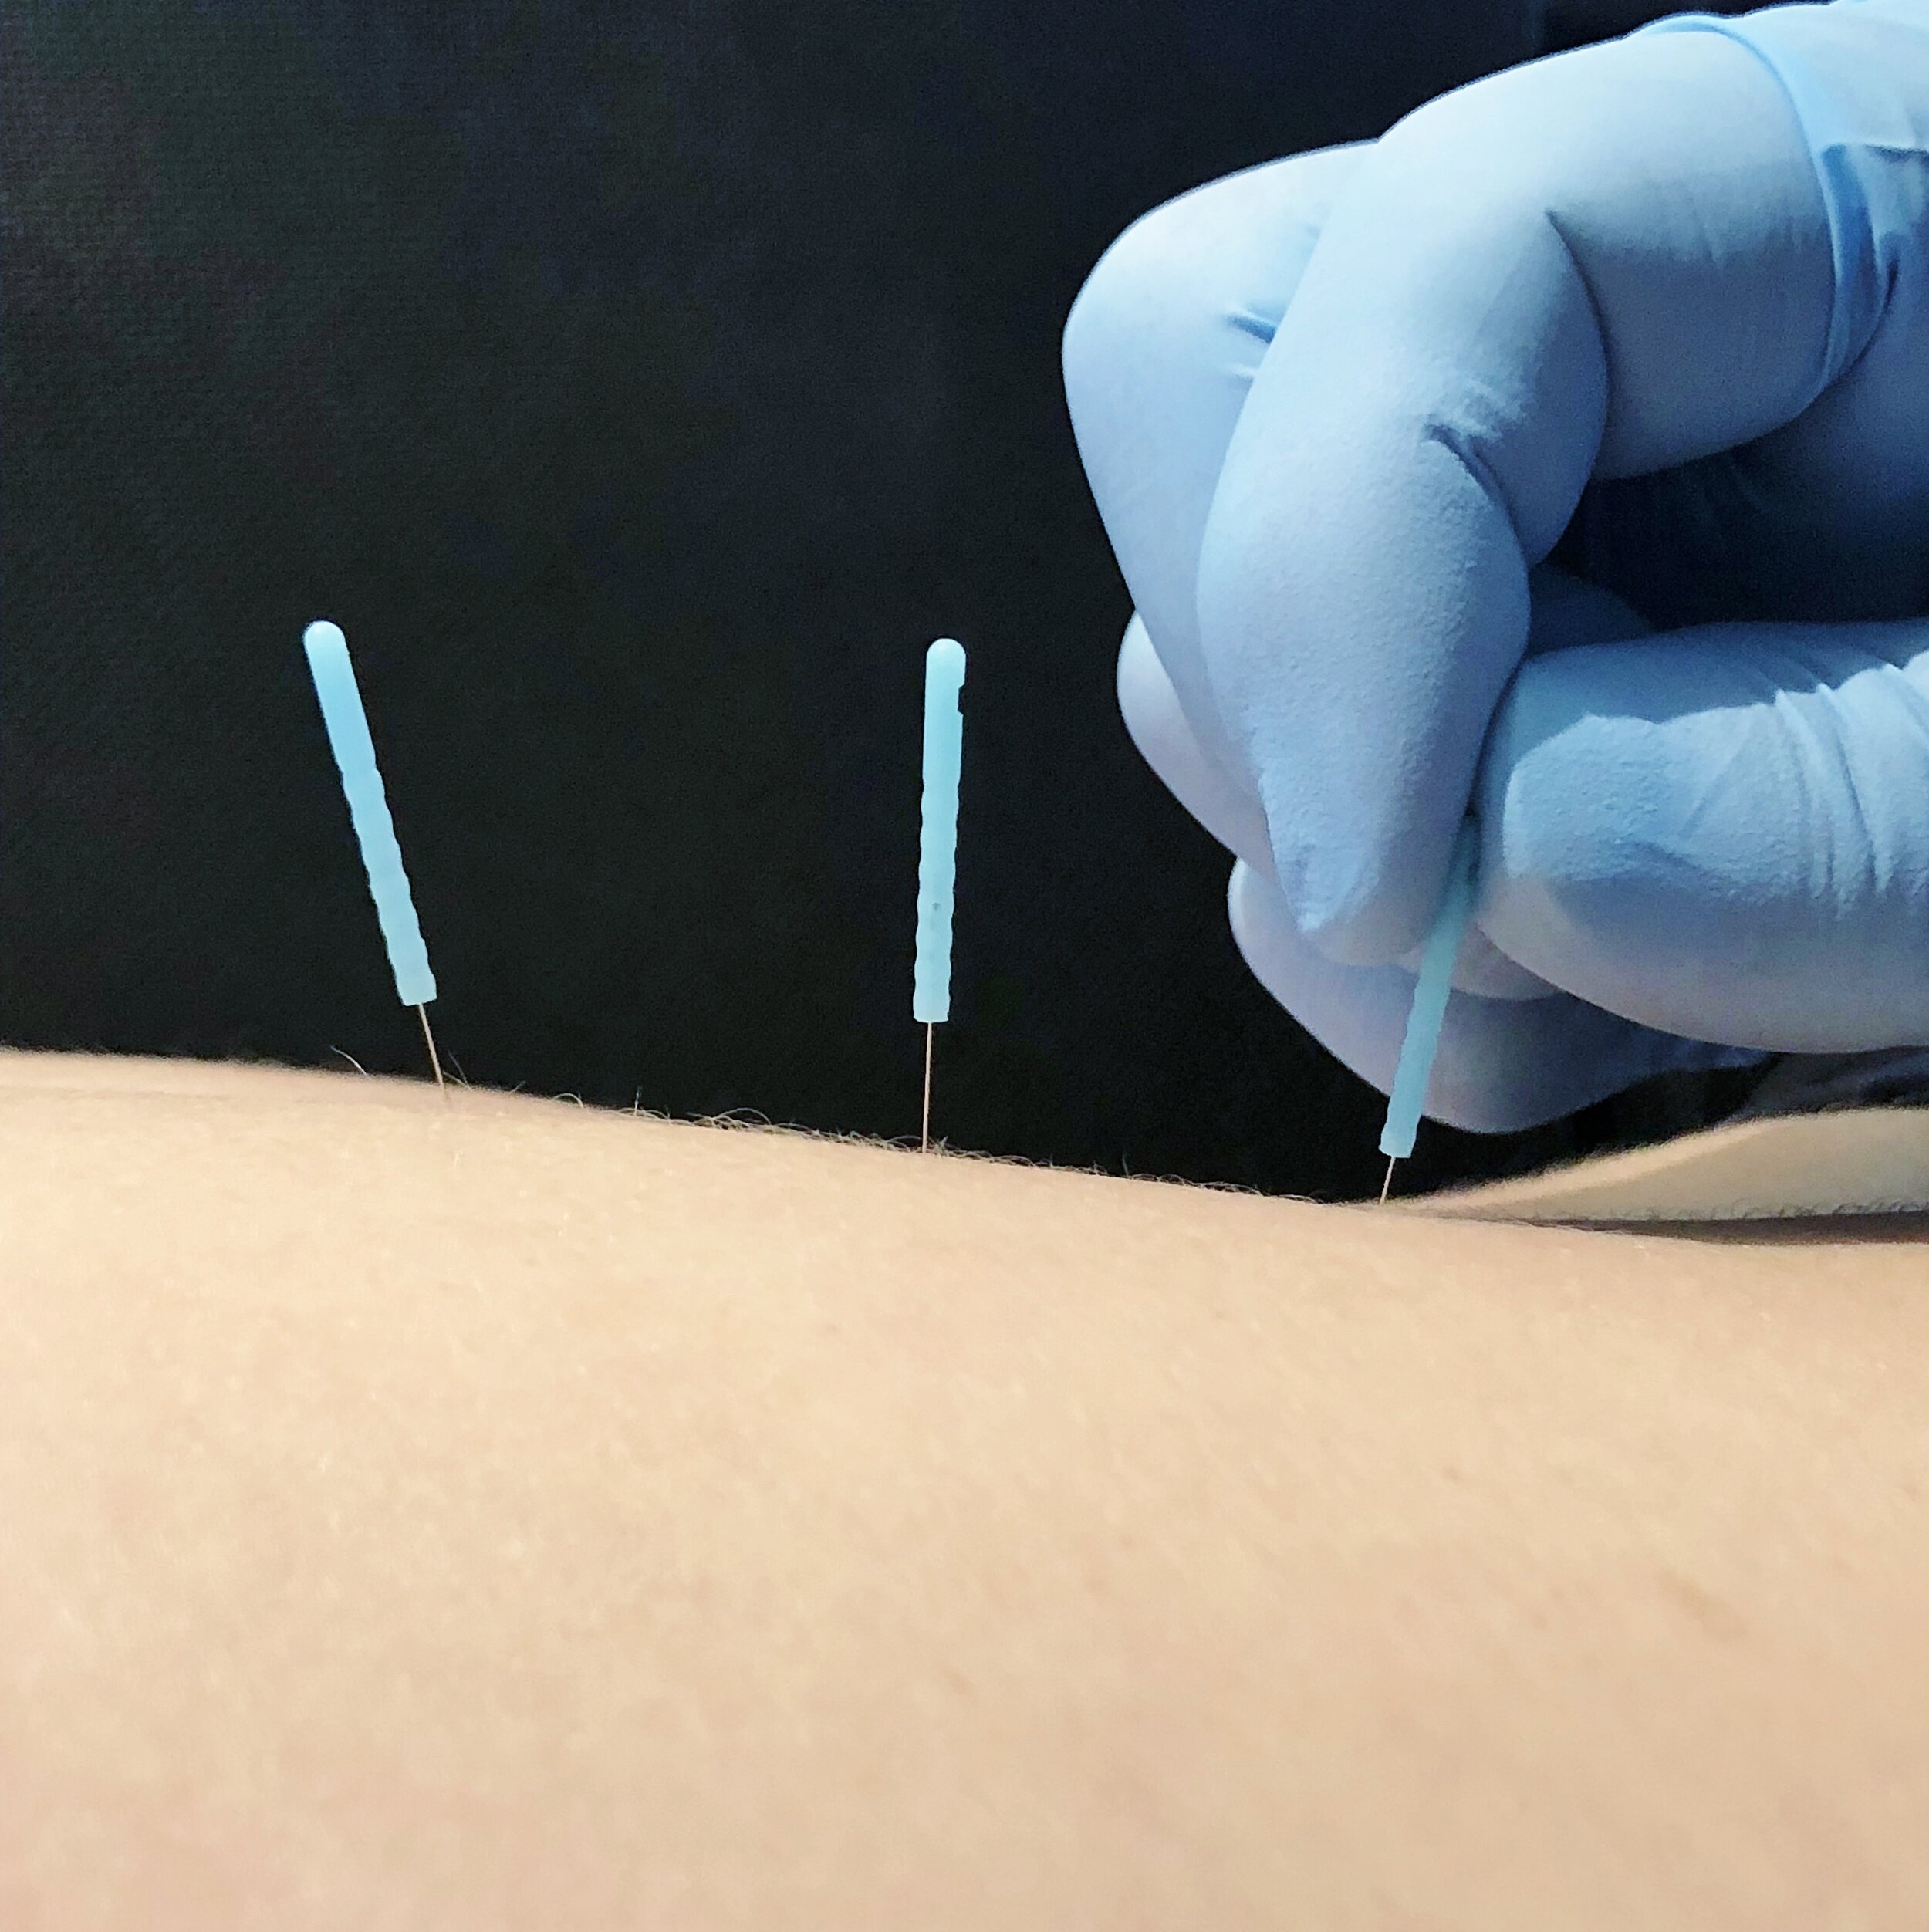

pictures of dry needling

What Is Dry Needling?

Dry needling – Isn’t that like acupuncture?

What is Dry Needling? – Professional Physical Therapy Houston

What is Dry Needling? – Advanced Physical Therapy Specialists

What Is Dry Needling? – [𝗣]𝗥𝗲𝗵𝗮𝗯

What is Dry Needling and how can it help? – Total Sports Therapy

What is dry needling? – Momentum Physical Therapy | Pueblo, CO

Everything You Need To Know About Dry Needling – PRO Therapy

What is dry needling and how can it benefit me? – MediPhysio